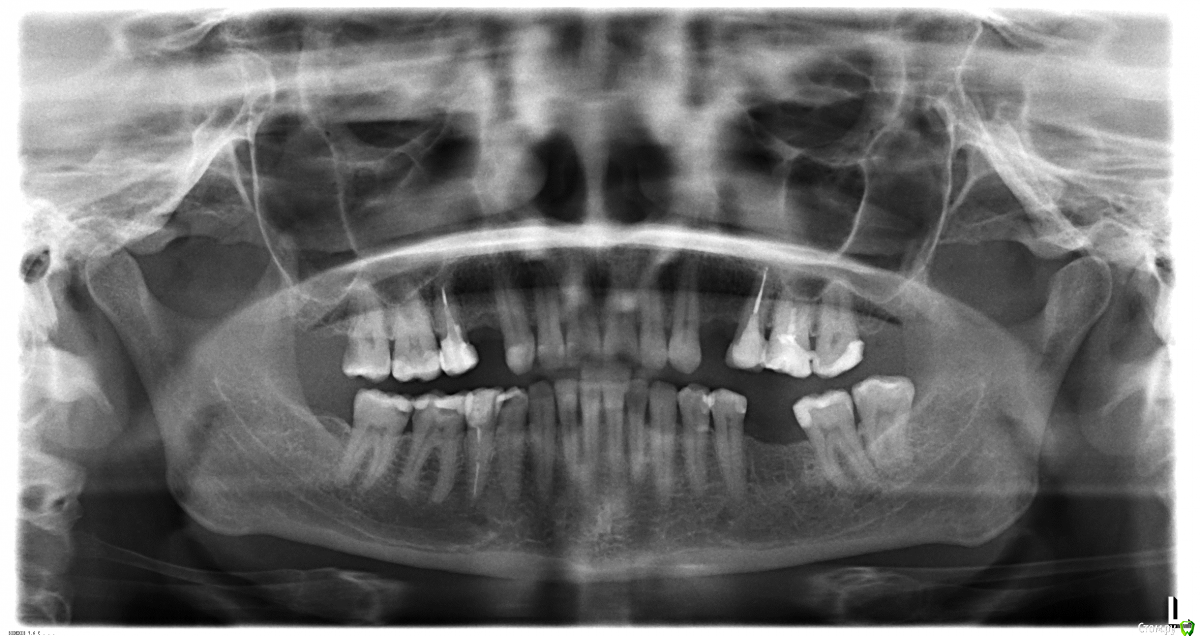

LediVinter Опубликовано 17 июля, 2018 Поделиться Опубликовано 17 июля, 2018 Здравствуйте! 1. У двух нижних зубов слева непонятная ситуация. Делаем прицельный снимок и врач сомневается (кариес ли межзубной под пломбами или изолирующие прокладки). Может сделать клкт?, а если это кариес( прочитала ,что при нем делать клкт нельзя)??? 2. На этой же стороне внизу зуб с стекловолоконным штифтом(постоянное чувтсво, что он мешает. в положении лежа давящее чувство в области кости нижней челюсти. Может переделать его или же сначала сделать клкт, по снимкам врач ничего не видит???) 3.Если возможно посоветцйте стоматолога (эндодонта) в Химках или в Москве. Спасибо! Ссылка на комментарий

CRAZYDUCK Опубликовано 18 июля, 2018 Поделиться Опубликовано 18 июля, 2018 Внизу указала стрелками - скорее всего кариес , на изолирующую не похоже . Особенно контактная дистальная поверхность 6 зуба ( вряд ли туда тоже изолирующую налили от души). Кариес ещё с этой стороны на верхнем зубе . Ссылка на комментарий

Zlata-doctor Опубликовано 19 июля, 2018 Поделиться Опубликовано 19 июля, 2018 и 44 тоже 1 Ссылка на комментарий